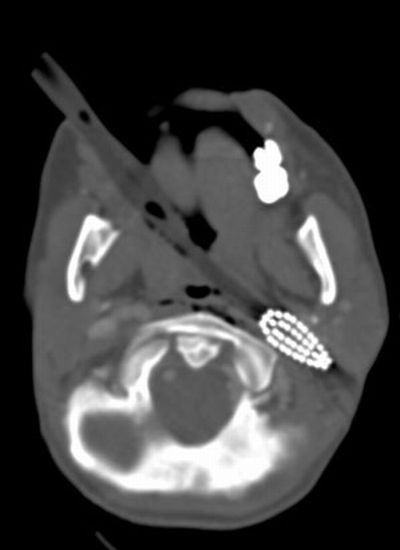

Radiografii terifiante: foarfece in cap, cuie in gat si furculite in mana

Surublenite infite in cap, plamani "dotati" cu cuie sau laringe "presarat" cu foarfece. Sunt numai cateva dintre cele mai ingrozitoare radiografii cu care s-au confruntat medicii de-a lungul timpului.

Iata mai jos o serie cu unele dintre cele mai "spectaculoase" radiografii.